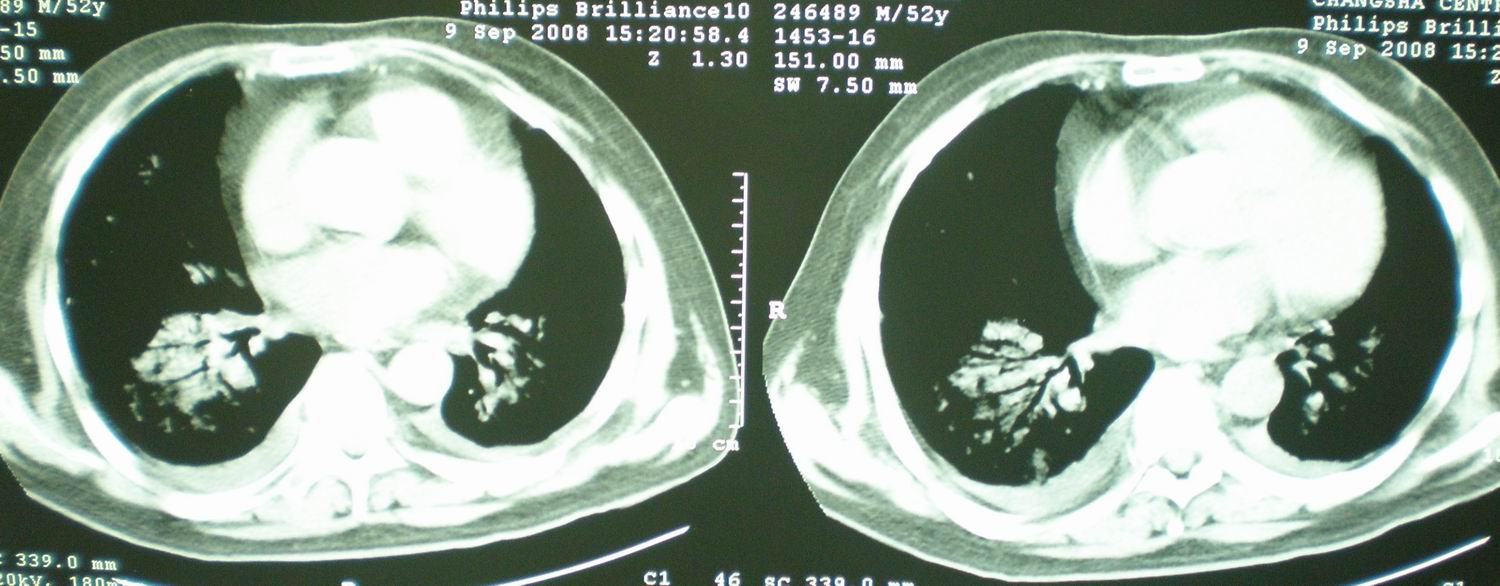

2008年9月18日ct片